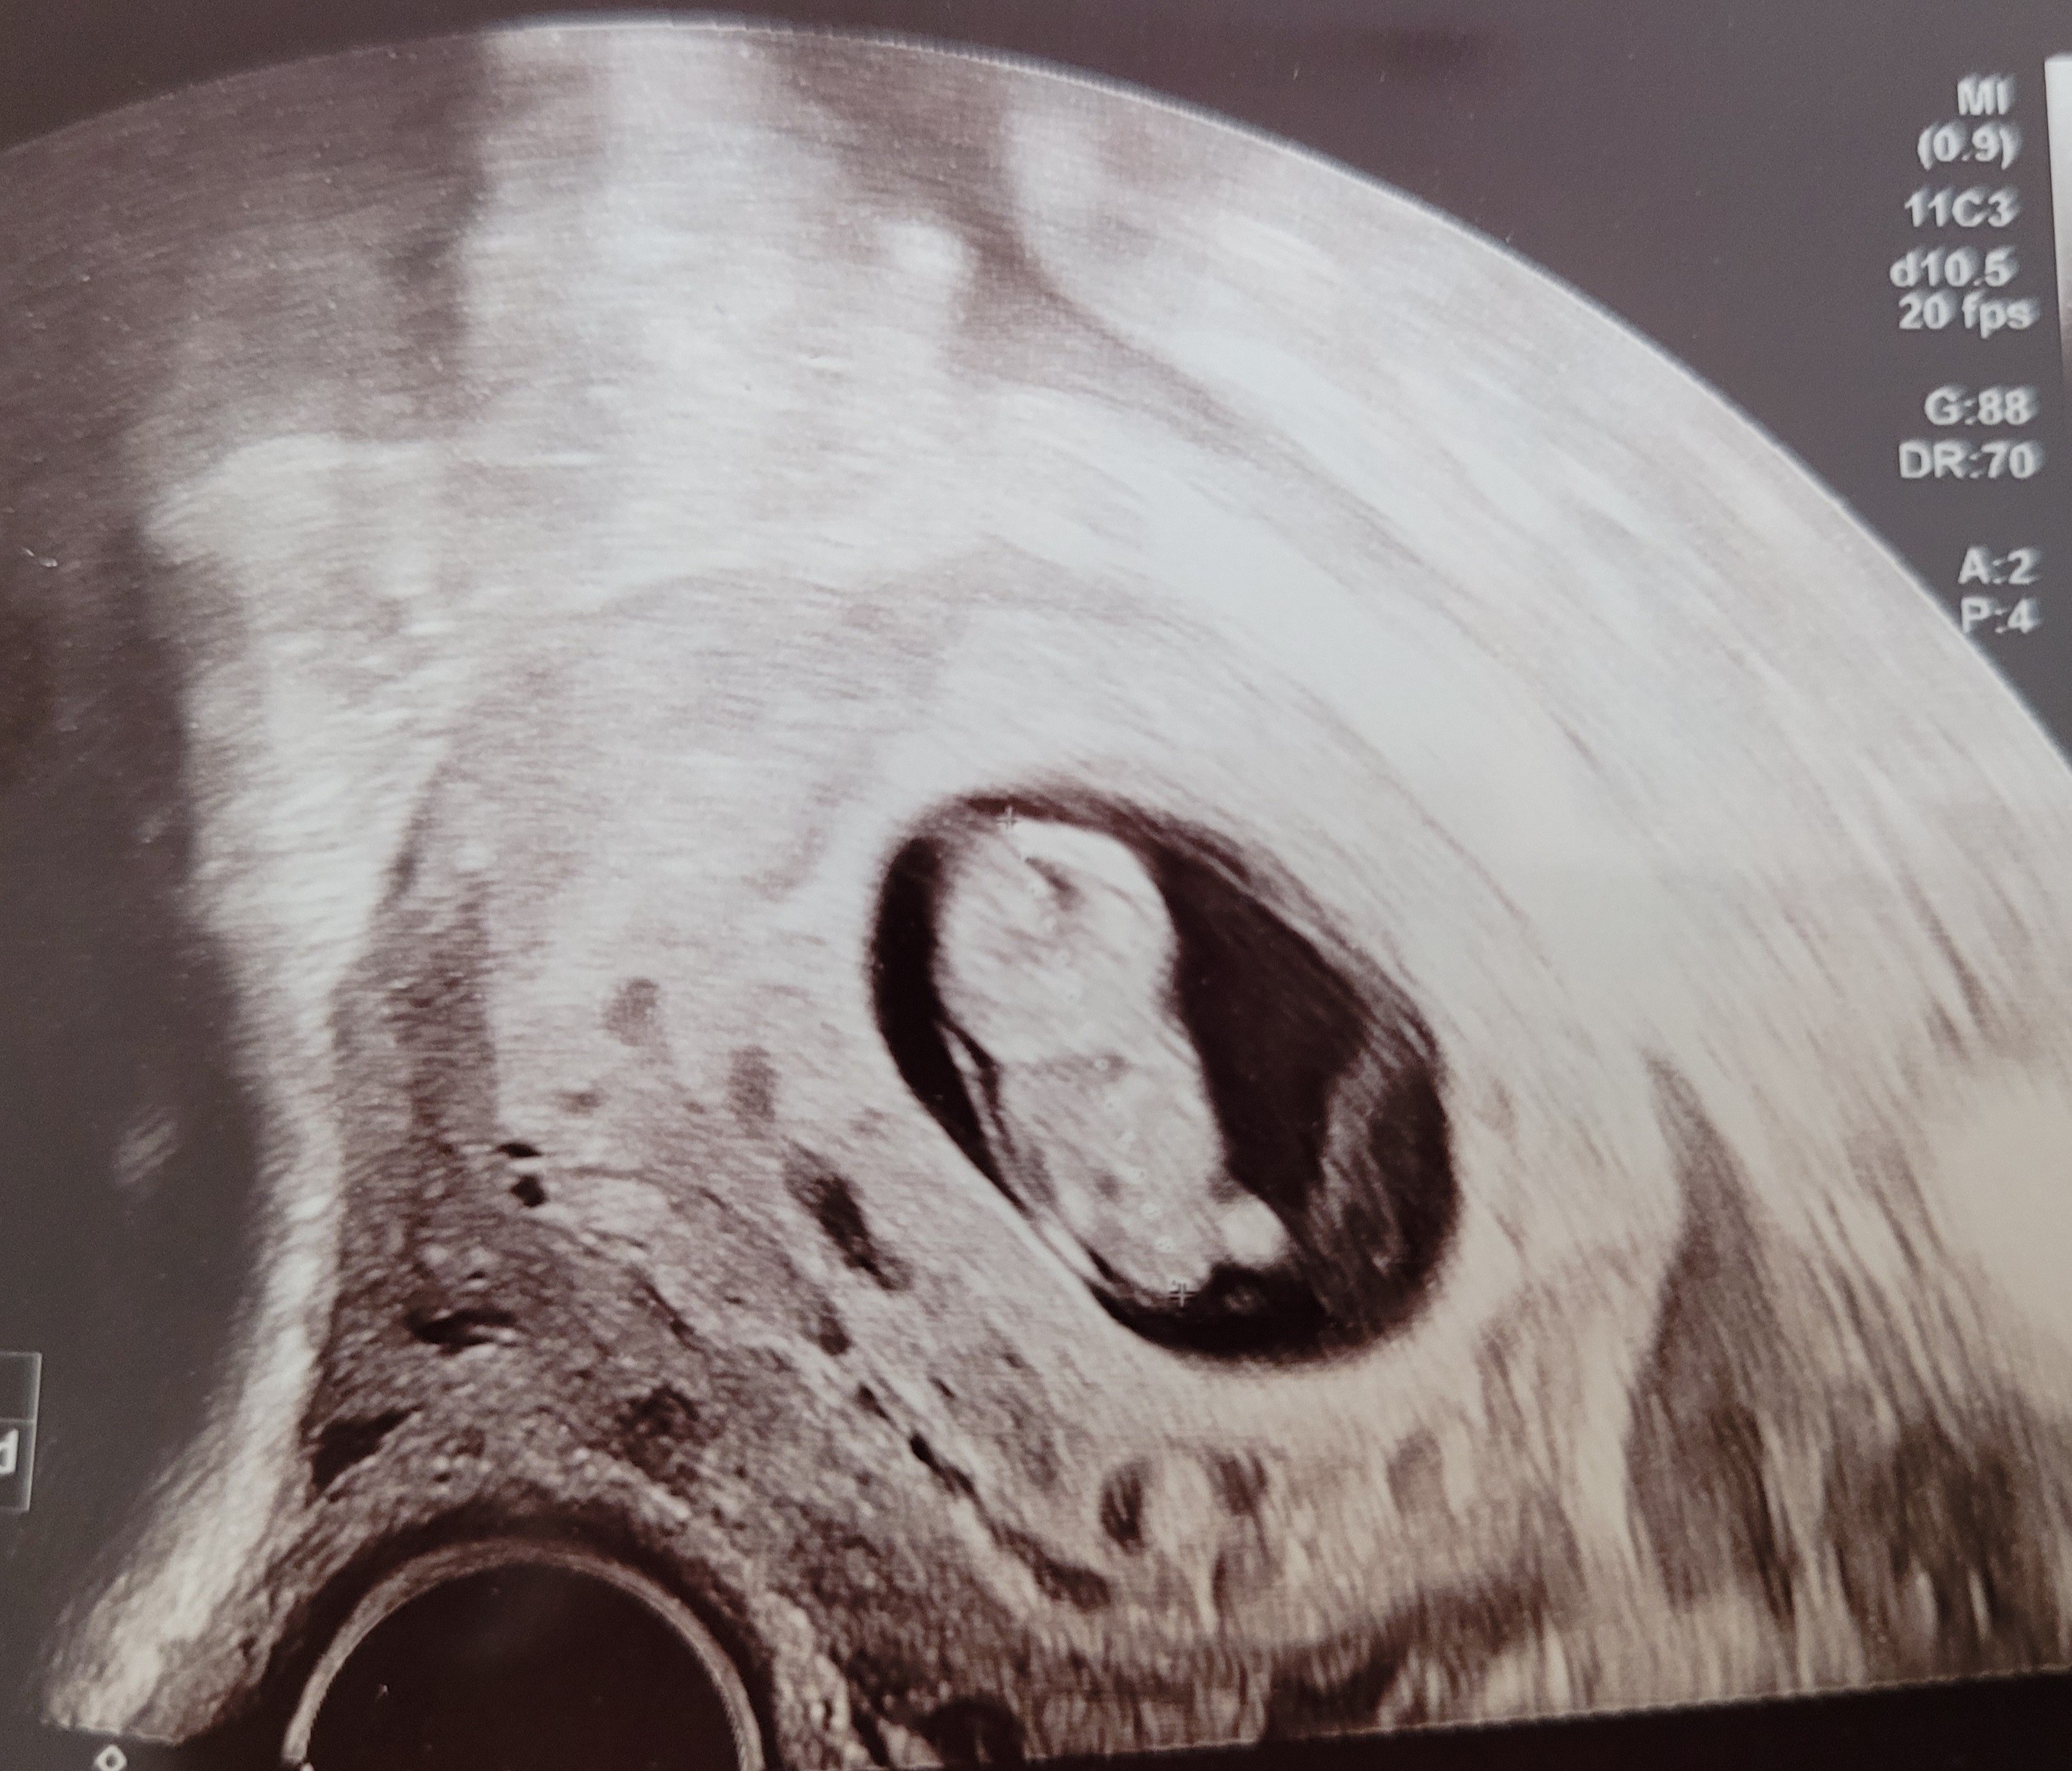

Ciaza zywa, 2,5 cm człowieka 😍

Mam się oszczędzać z racji, że łożysko jest bardzo nisko.

Załączniki

• 20220307_124101.jpg

20220307_124101.jpg

1,2 MB · Wyświetleń: 86